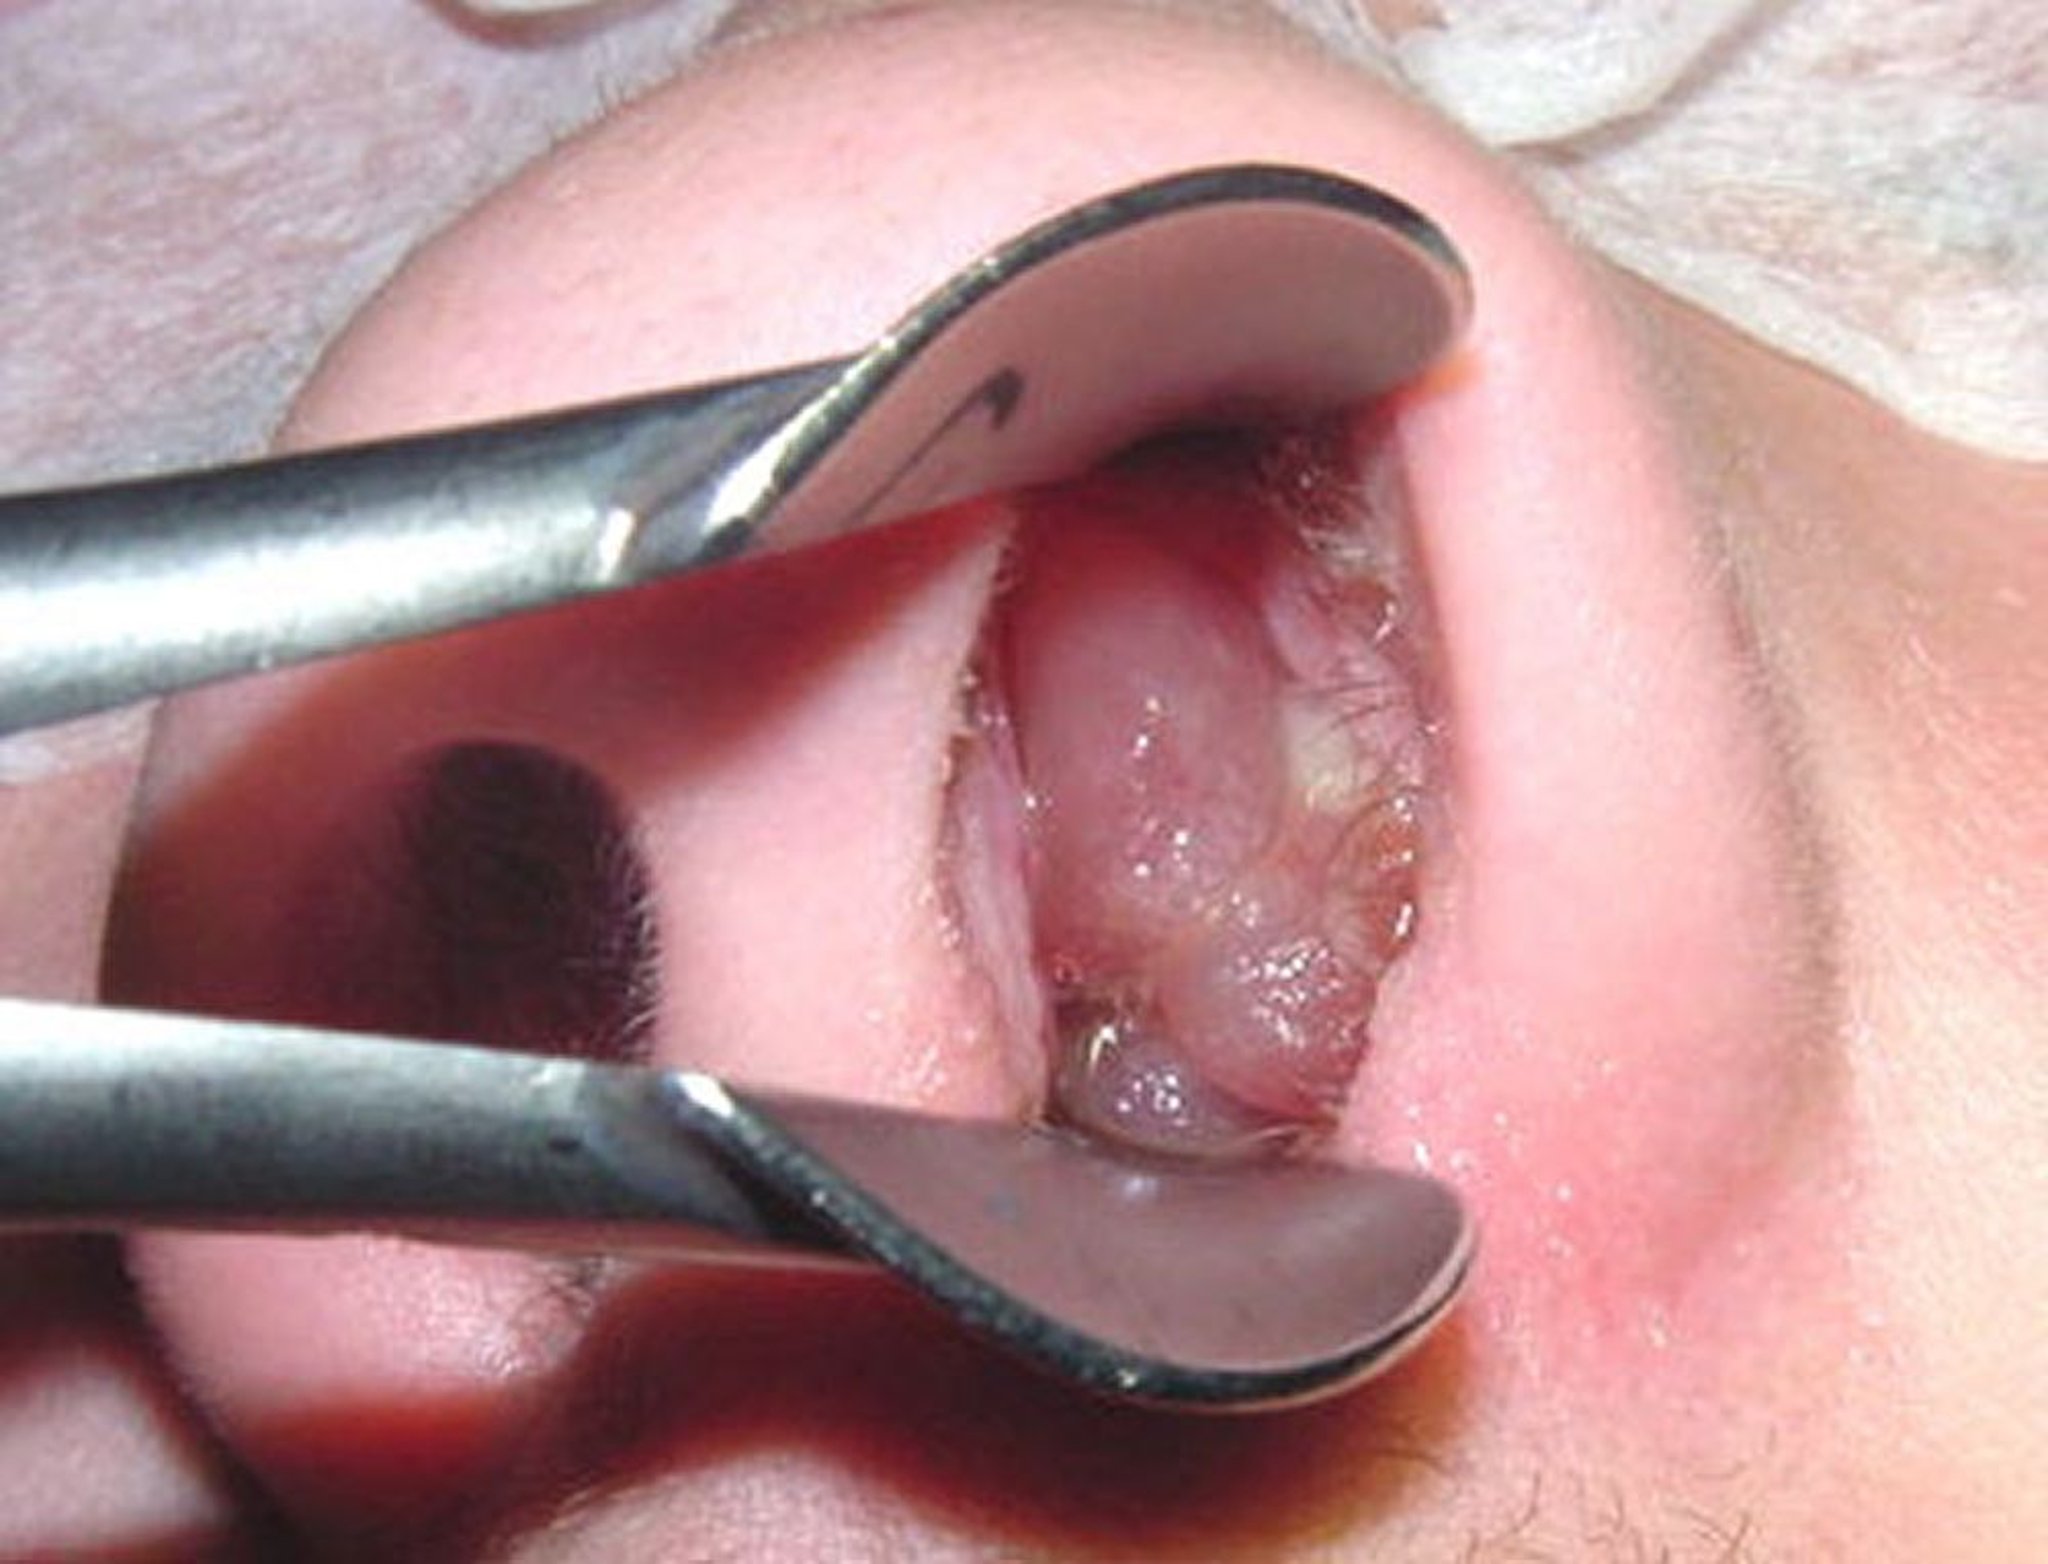

Зрелый носовой полип может напоминать очищенный виноград без косточек.

Image provided by Bechara Ghorayeb, MD.